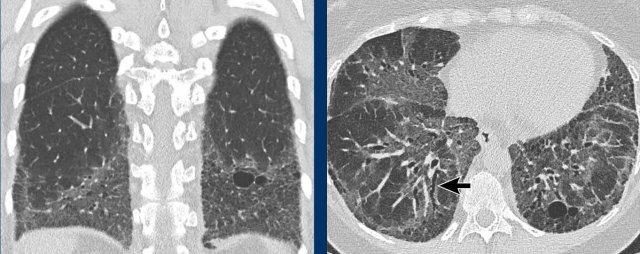

Hình ảnh

- Các nang BHD. Một số nang tiếp giáp với màng phổi (mũi tên vàng) hoặc các rãnh liên thùy. Các nang ở vùng phổi thấp cũng có thể gặp trong LIP. Khí phế thũng cạnh vách liên tiểu thùy có phân bố ưu thế ở vùng phổi trên.

- Phân bố ưu thế ở vùng phổi thấp và các nang hình tam giác (đầu mũi tên) trong BHD.

- Lưu ý hình ảnh rất tinh tế với phân bố ưu thế ở vùng phổi thấp.

- Các nang BHD điển hình

Đây là hình ảnh của một phụ nữ 56 tuổi, có tiền sử tràn khí màng phổi tái phát và hiện tại nhập viện lần này cũng vì tràn khí màng phổi (mũi tên).

Hãy phân tích hình ảnh.

Đây là các nang thực sự hay các tổn thương giả nang?

Đây là phát hiện tình cờ hay bạn cho rằng đây là bệnh phổi dạng nang?

Chẩn đoán có khả năng nhất là gì?

Nhận xét hình ảnh

Có nhiều nang thành mỏng – hơn bốn nang. Lưu ý vị trí phân bố gần các rãnh liên thùy và ở ngoại vi phổi.

Kết luận

Đây là trường hợp hội chứng Birt-Hogg-Dubé (BHD).

Bàn luận

Hai bệnh phổi dạng nang thường biểu hiện bằng tràn khí màng phổi là LAM và BHD.

LAM biểu hiện là các nang đơn thuần, thành mỏng, hình tròn hoặc bầu dục, đều đặn với phân bố lan tỏa.

Vị trí ngoại vi và cạnh rãnh liên thùy của các nang BHD thường tạo ra các góc nhọn, khiến chúng có hình dạng thấu kính.

Khi các nang có hình ảnh đặc trưng này, chúng có độ đặc hiệu cực kỳ cao cho chẩn đoán hội chứng Birt-Hogg-Dubé.

Đây là một trường hợp khác của hội chứng Birt-Hogg-Dubé.

Các nang có vị trí điển hình ở ngoại vi phổi gần trung thất (mũi tên đen) và gần rãnh liên thùy (mũi tên trắng).

Đây là một trường hợp minh họa khác với rất ít nang nhỏ ở bệnh nhân mắc hội chứng Birt-Hogg-Dubé.

Đôi khi cần phải quan sát rất kỹ các trường phổi để không bỏ sót các nang và bỏ lỡ chẩn đoán BHD.

Trong trường hợp này, có thể hình dung rằng nếu CT được thực hiện vì lý do khác, người đọc có thể dễ dàng bỏ sót những nang nhỏ này.

Cần nhớ rằng khi phát hiện hơn bốn nang và chúng thực sự là nang, cần phải xử lý các phát hiện này.

Những bệnh nhân này nên được chuyển đến bác sĩ chuyên khoa hô hấp để đánh giá thêm.

Bệnh nhân này được chụp CT để đánh giá khối u thận.

Trong báo cáo chẩn đoán hình ảnh, các nang trong phổi được mô tả là bóng khí (bullae).

Tuy nhiên, các nang này là nang BHD điển hình ở ngoại vi phổi, trong khi bóng khí thường gặp ở bệnh nhân khí phế thũng và có vị trí ở các trường phổi trên.

Đặc biệt khi chỉ thấy một vài nang, hãy nghĩ đến BHD.

Gia đình bệnh nhân cần được tầm soát hội chứng BHD và khối u thận.

Cuối cùng là một trường hợp BHD nặng hơn với các nang kích thước lớn hơn.

Bệnh nhân này nhập viện vì tràn khí màng phổi.

Lưu ý ống dẫn lưu (mũi tên).